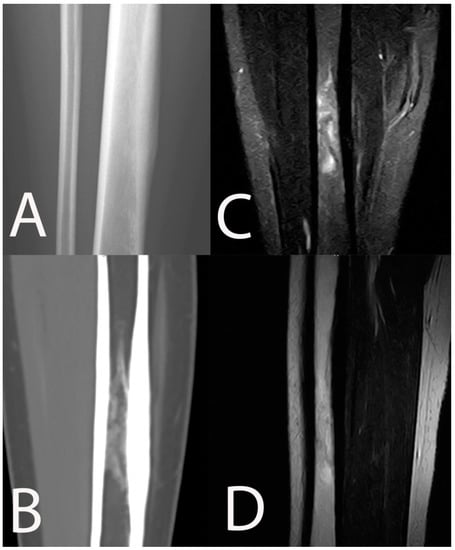

8. Fracture Related Infection (FRI)

- Lee, Y.J.; Sadigh, S.; Mankad, K.; Kapse, N.; Rajeswaran, G. The imaging of osteomyelitis. Quant. Imaging Med. Surg. 2016, 6, 184–198. [Google Scholar] [CrossRef] [Green Version]

- Bühne, K.H.; Bohndorf, K. Imaging of posttraumatic osteomyelitis. Semin. Musculoskelet. Radiol. 2004, 8, 199–204. [Google Scholar] [CrossRef] [PubMed]

- Govaert, G.A.; IJpma, F.F.; McNally, M.; McNally, E.; Reininga, I.H.; Glaudemans, A.W. Accuracy of diagnostic imaging modalities for peripheral post-traumatic osteomyelitis–a systematic review of the recent literature. Eur. J. Nucl. Med. Mol. Imaging 2017, 44, 1393–1407. [Google Scholar] [CrossRef] [PubMed] [Green Version]